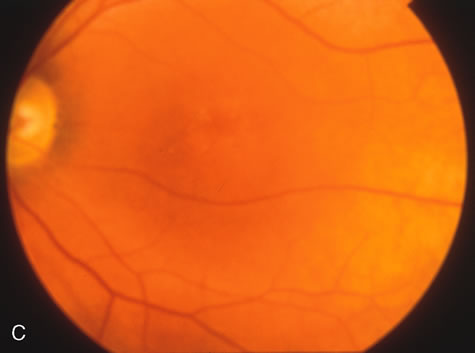

Fig. 1. Retinitis pigmentosa. A. A typical area of bone spicule pigmentation. B. Diffuse dye leakage is apparent throughout the posterior pole. C. The early angiogram shows dilated and irregular retinal radial peripapillary capillaries and perifoveal retinal capillaries. D. Leakage from these vessels are evident in the late angiogram.

Of more clinical importance is the role of FA in the diagnosis and treatment of cystoid macular edema (CME) (Fig. 1C and D). Stereoscopic FA indicates that the leakage, which may be diffuse or have the typical petaloid stellate appearance of CME, can come from the perifoveal retinal capillaries, from the choroid through the RPE, or from a combination of both sources.4 With the recent suggestion that CME in RP may be successfully treated with acetazolamide,5, 6 FA is thus important to document the diagnosis of CME, establish the origin(s) of leakage, and follow patients during and after therapy.